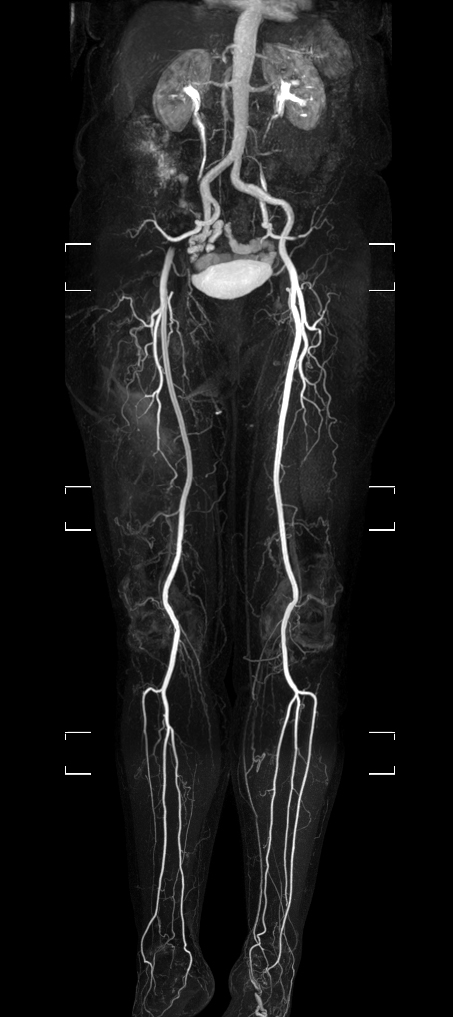

Patient with a known stent in the abdominal veins. Subtraction-less mDIXON MRA run-off is performed using a combination of Compressed SENSE and enhanced gradient strength to increase both in-plane and through-plane spatial resolution. The station covering the feet has been rescanned with a Compressed SENSE factor of 14, resulting in a time resolved scan with a dynamic time of only 4 seconds.

mDIXON MRA (MIP)